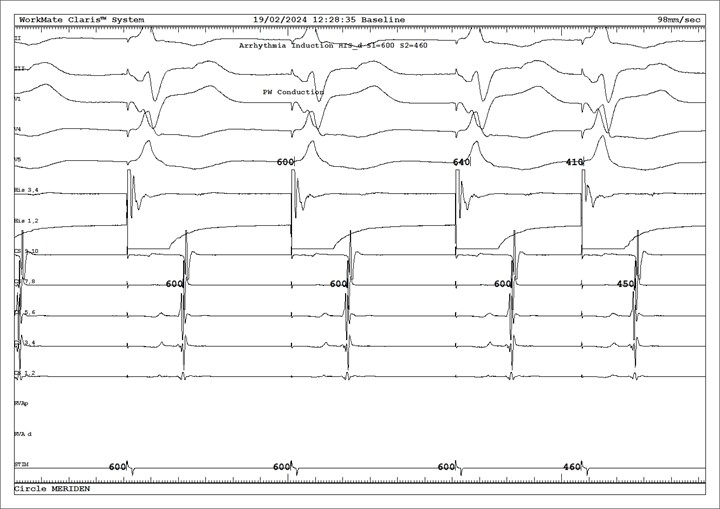

When the patient was back in sinus rhythm, a retrograde curve was performed (by pacing from the right ventricle, similar to that of VOP but at a slower rate), which showed eccentric atrial activation (Figure 2). Putting it all together, the mechanism of this patient’s NCT is most likely to be an AVRT from a concealed left accessory pathway.

Figure 2. Retrograde curve of the EP study, which showed eccentric atrial activation suggesting the presence of a concealed left accessory pathway.

Electrocardiogram labels from top to bottom: Leads II, III, V1, V4, V5. His 3-4 (proximal), His 1-2 (distal), CS 9-10 (proximal) to CS 1-2 (distal), RVA proximal, RVA distal.